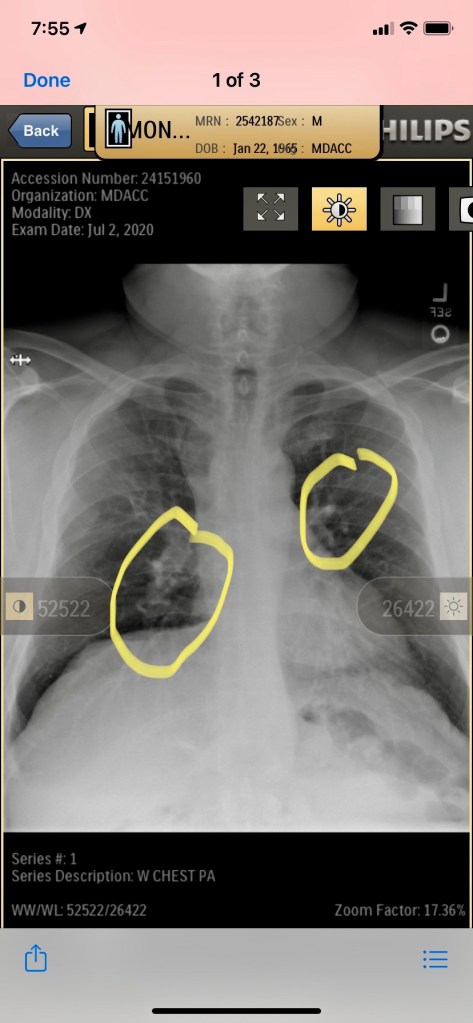

Here is the imaging that this report refers to:

This is the X-ray. WE WERE TOLD THIS WAS A CLEAR Xray! A dear friend of Martin’s, Jamie, works in the radiation department. We send this to her and she circles what should have been noted from the beginning.

I went around town and gathered every medical paper on Martin that had been written in the last 5 years to show the doctor as much of Martin’s medical history as possible. Mid-January they are doing a biopsy, but before they start they popped the image CD with Martin’s xray in their machine to look at it. Immediately, Martin was asked what took him so long to come to MD Anderson. He told the dr doing the biopsy that he just found. “It is pretty clear you have something growing on your lungs in this xray from July”- NOW IT IS MID-JANUARY! Martin is wheeled back to the recovery area where I am waiting and he tells me this. WHAT??? How can this happen? In true Wendi mode, I immediately sent off a message to Rebecca Dees. I have included the screenshots below: